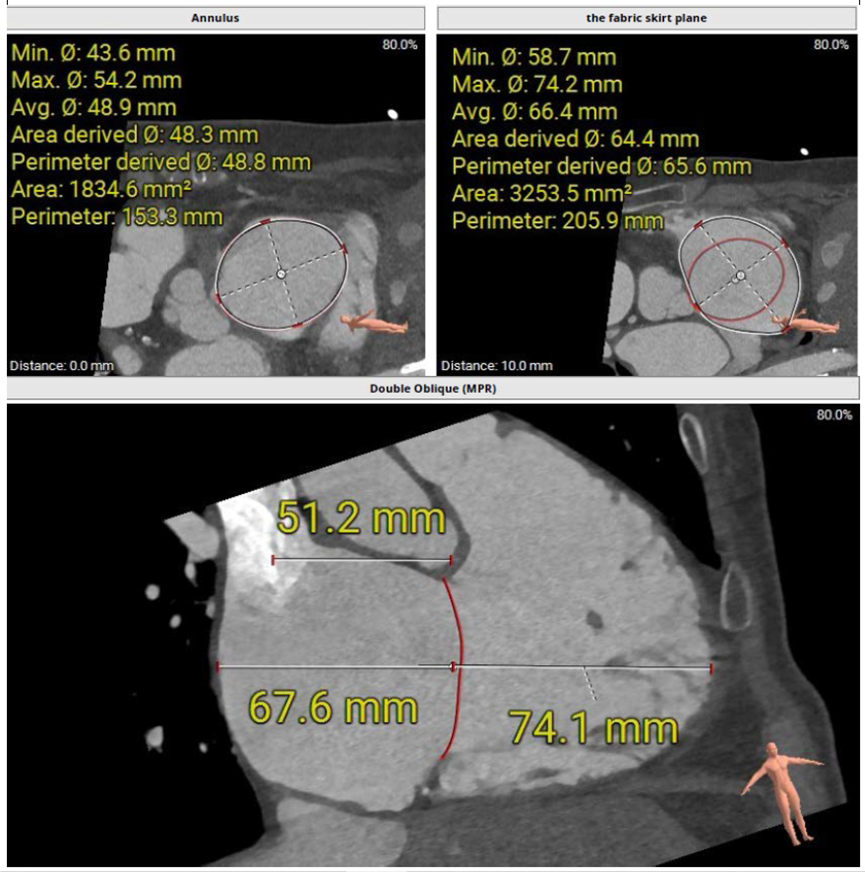

術(shù)前CT評估三尖瓣瓣環(huán)大小

該例患者為79歲女性,NYHAⅢ級,心衰癥狀顯著,藥物(大劑量利尿劑)治療9個月后仍出現(xiàn)頑固性踝關(guān)節(jié)水腫。術(shù)前超聲心動圖提示三尖瓣重度反流(5+),右房右室擴大,三尖瓣瓣環(huán)擴張合并嚴重三尖瓣葉栓系,TAPSE 1.9cm,gap 23.2mm,PASP 30~35mmHg,LVEF 58%。